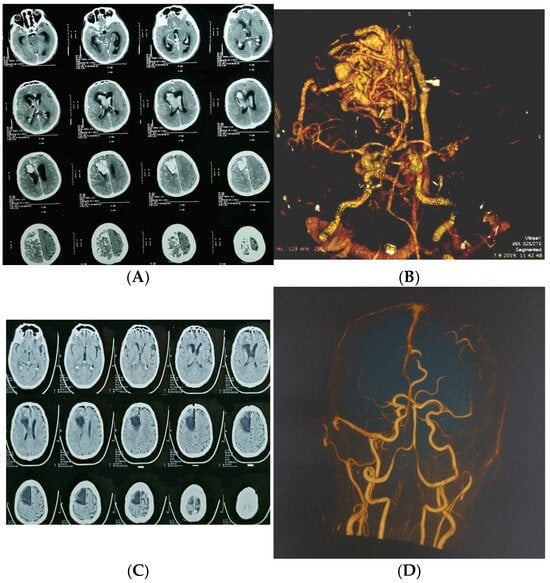

Figure 2.

A 65-year-old man presented with severe headache, nausea, vomiting, and impaired consciousness progressing to sopor. (A) Axial CT showing large ruptured right frontal arteriovenous malformation (AVM); (B) urgent CT angiography confirmed diagnosis; (C) postoperative computed tomography; (D) postoperative computed tomography angiography.